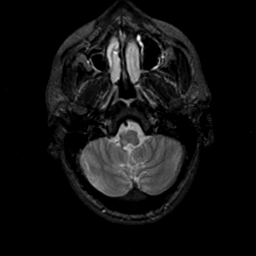

MR Study #19, August 25, 1991 -- Slice #7

[Home][Help][Clinical][Tour 1][Tour 2] Slice 7